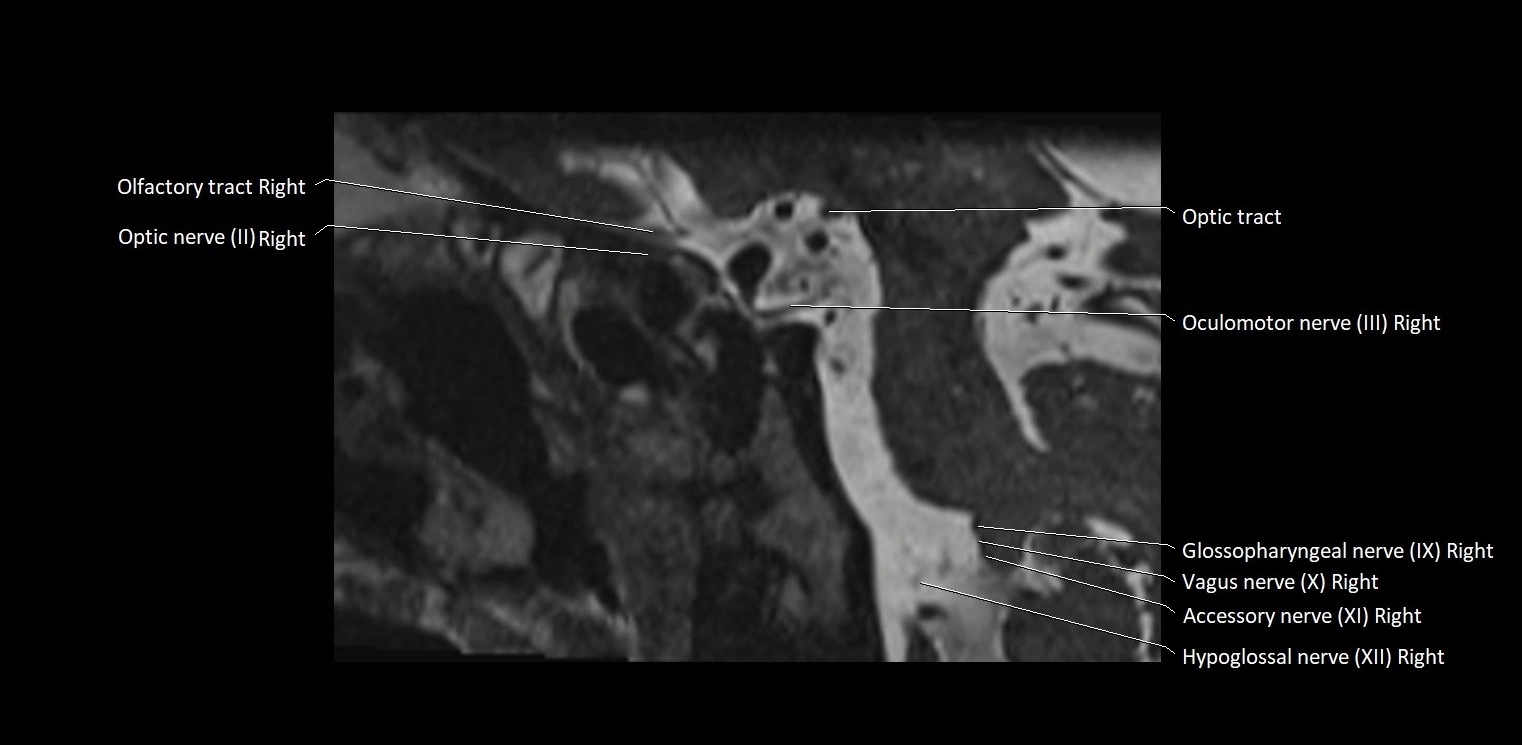

MRI Appearance

• The abducens nerve is a small, thin, linear structure

• Best visualized on high-resolution T2-weighted 3D MRI sequences (e.g., FIESTA or CISS)

• Seen as a hypointense (dark) line running from the brainstem at the pontomedullary junction, traversing the prepontine cistern, and entering Dorello’s canal under the petrosphenoidal ligament, then into the cavernous sinus, and finally the orbit

• May be challenging to visualize in standard MRI due to its small size

• Pathology may be inferred by absence, displacement, or enhancement of the nerve